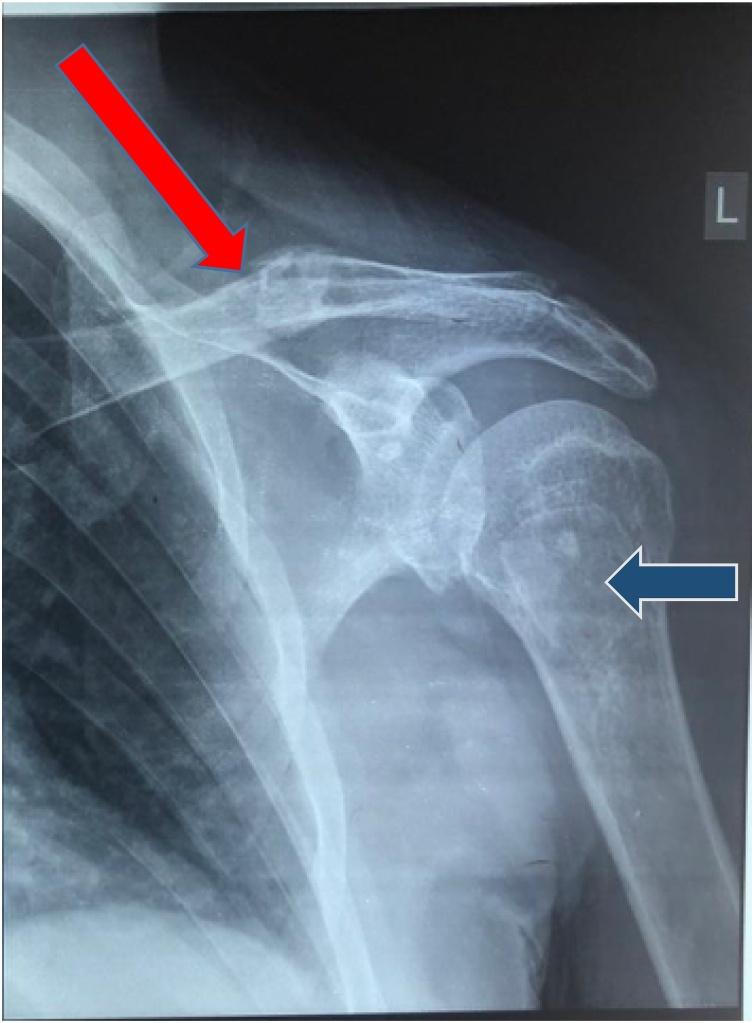

A 41 years old previously healthy male patient with undetectable surgical and familial history presenting with left clavicle fracture by mild trauma. He was diagnosed for primary hyperparathyroidism after the finding of multiple bony lesions and elevated serum calcium and Parathyroid hormone. Preoperative imaging aided in diagnosis of a parathyroid lesion and secondary bone resorption lesions (brown tumors). After adequate medical treatment and preparation, selective right lower parathyroidectomy was held, and the final pathology came with a giant parathyroid adenoma.

一名41岁既往健康的男性患者,无手术及家族病史,因轻度外伤致左锁骨骨折就诊。在发现多处骨病变以及血清钙和甲状旁腺激素升高后,他被诊断为原发性甲状旁腺功能亢进。术前影像学检查有助于诊断甲状旁腺病变及继发性骨吸收病变(棕色瘤)。经过充分的药物治疗和准备后,实施了选择性右下甲状旁腺切除术,最终病理结果为巨大甲状旁腺腺瘤。